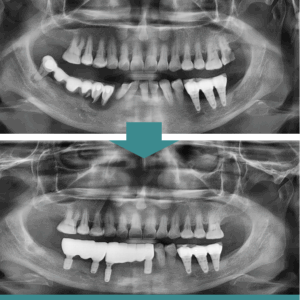

단대오거리치과, 전체 임플란트로 건강한 삶을 회복시켜 드리는 심한 충치나 파절, 외상으로 인한 손상이 아니더라도 치아를 발치하게 되는 경우가 있는데요. 바로 치주 질환에 의한 발치입니다. 치주 질환은 우리나라 성인 인구의 70% 이상이 겪고 있을 만큼 매우 흔하게 나타나는 구강 질환으로, 치아를 지지하고 있는 잇몸과 치조골(잇몸뼈), 치주 인대 등에 염증이 생기는 질환을 더보기…